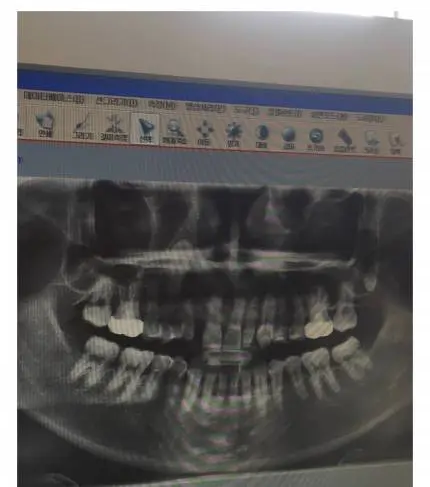

치과의사도 포기한 치아 레전드